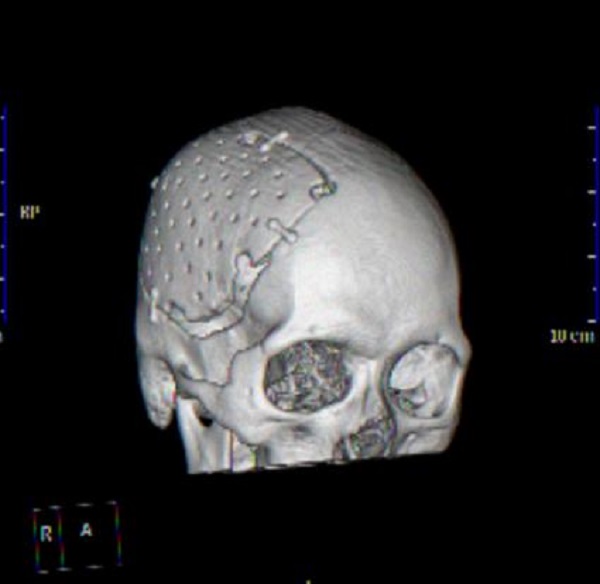

(自体颅骨修补后三维复建图,贴合人体正常生理解剖)

神经外科主任千超了解病情后,考虑到张先生还很年轻,对今后生活能力与生活质量要求较高,经过反复协商讨论,千超主任团队最终确定了术后保留患者自体骨瓣,待病情恢复好转后行自体颅骨修补方案,手术去除的骨瓣采用消毒及低温技术保存。1个多月前,张先生再次入院,千超主任医师团队按照既定方案,为张先生施行了自体颅骨修补术,手术过程顺利,术后,张先生头颅外观基本恢复正常,有效减轻了心理压力,让张先生重建了再次融入社会生活的自信与信心。